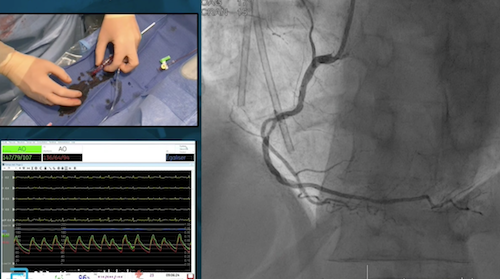

Le Pr Patrick Ohlman est ensuite revenu sur les apports de la Tomographie par Cohérence Optique (OCT) dans le diagnostic des maladies coronariennes, notamment pour le syndrome coronaire aigu. Par ailleurs, dans le cas d'un thrombus, l'angiographie donne une image lacunaire floue alors que l'OCT est parlante. Il a également rappelé quenl'OCT permet souvent de ne pas réaliser d'angioplastie inutile et qu'elle identifie mieux, d'autre part, le trajet du guide lorsque l'on a à faire à une dissection coronaire. Cette technologie permet enfin une optimisation du stenting en évaluant notamment les sous extension du stent ou sa mal-apposition lors de l'angioplastie.